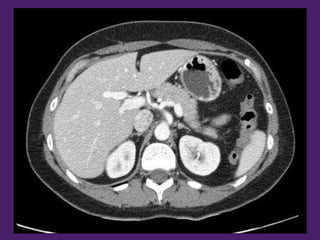

Páncreas

Arteria esplénica

Aorta

descendente

Vena cava

inferior

Lóbulo

derecho

del hígado

Fundus

gástrico

Pilares del

diafragma

Colon

Glándula

suprarrenal

derecha

Cuerpo